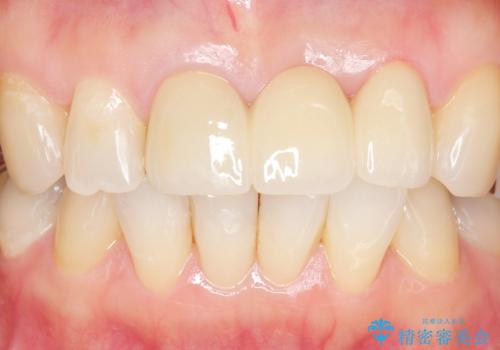

自然な仕上がりに喜んで頂けました。

モチベーションが上がりオフィスホワイトニングもご希望され、口元の印象が明るくなりました。

クラウンの種類:オールセラミッククラウン スタンダード